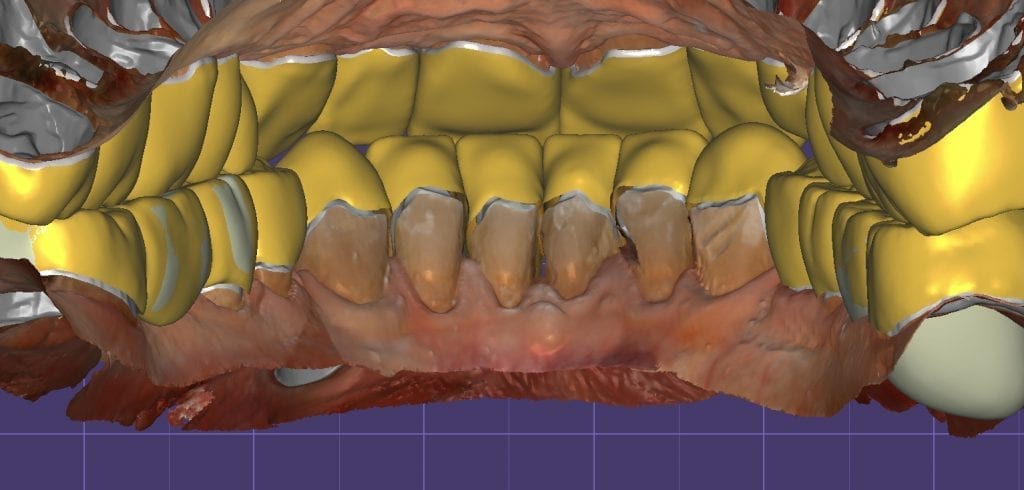

The digital models were then imported into a third party software where a library of tooth morphologies are available for the clinician to choose from.

Once the appropriate library is chosen, the digital wax ups are performed. In the subsequent photos you can see the transparent overlay of the wax-ups to the original position of the existing dentition